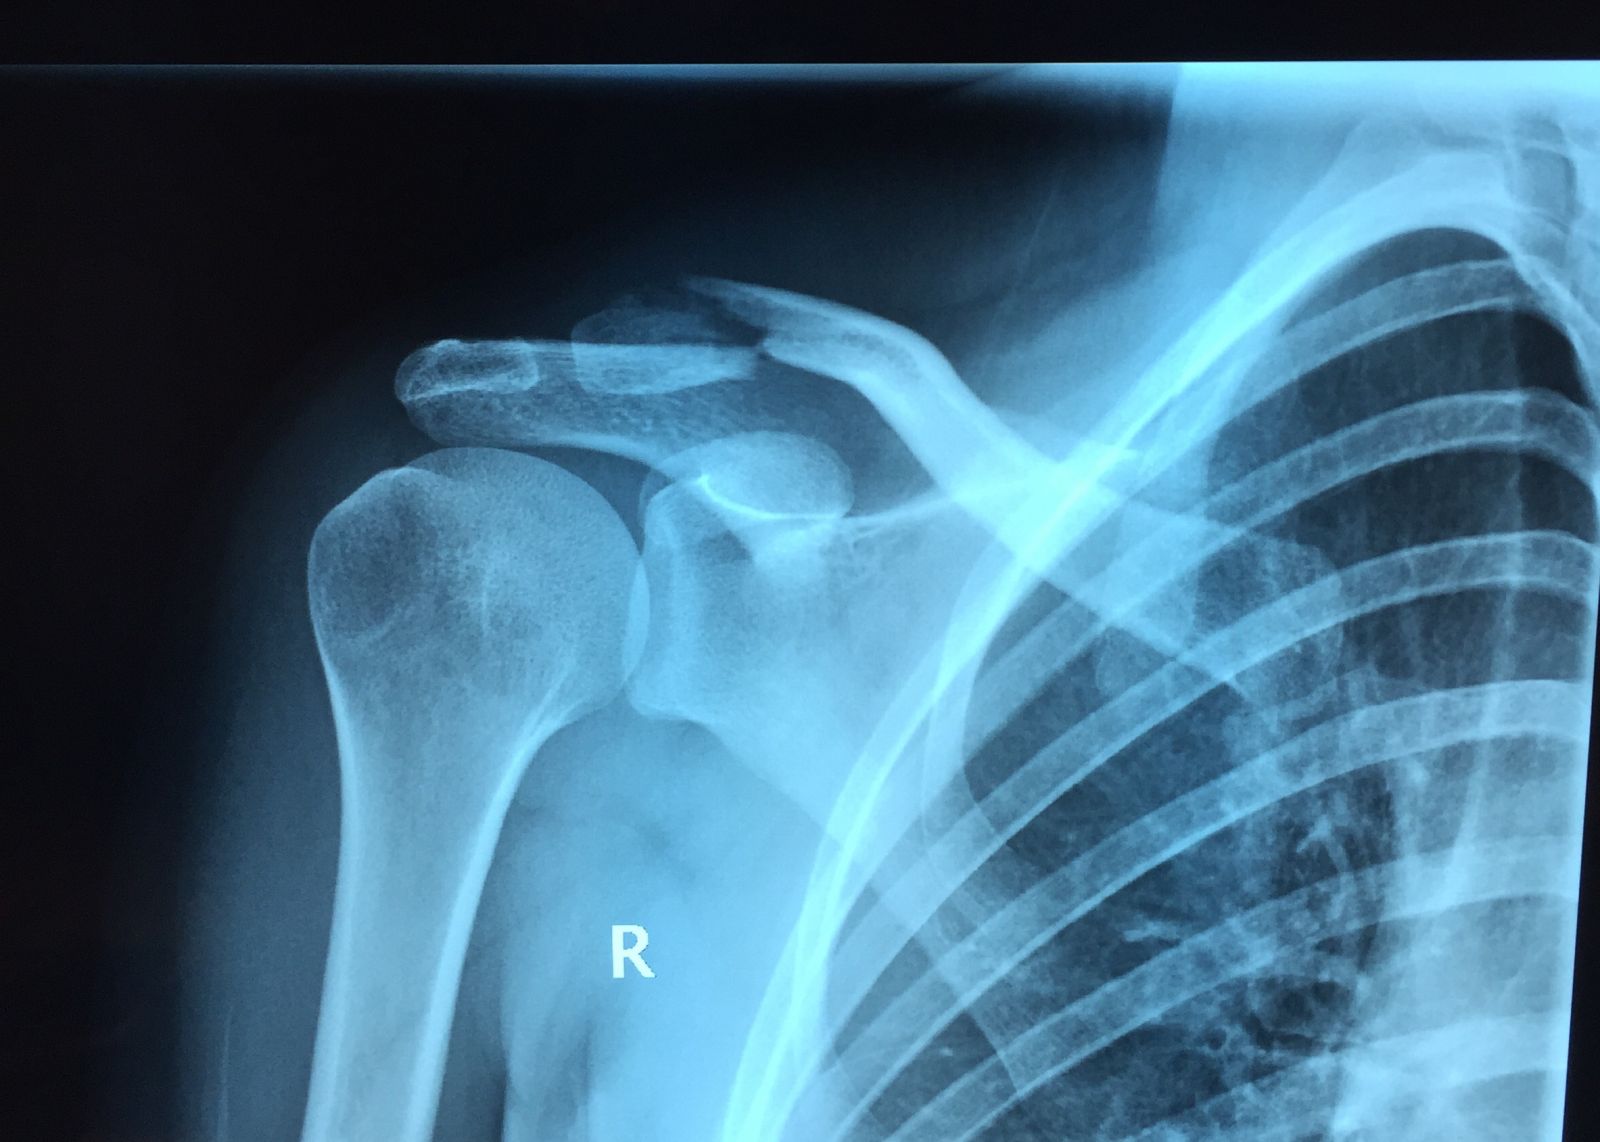

Προεγχειρητικά